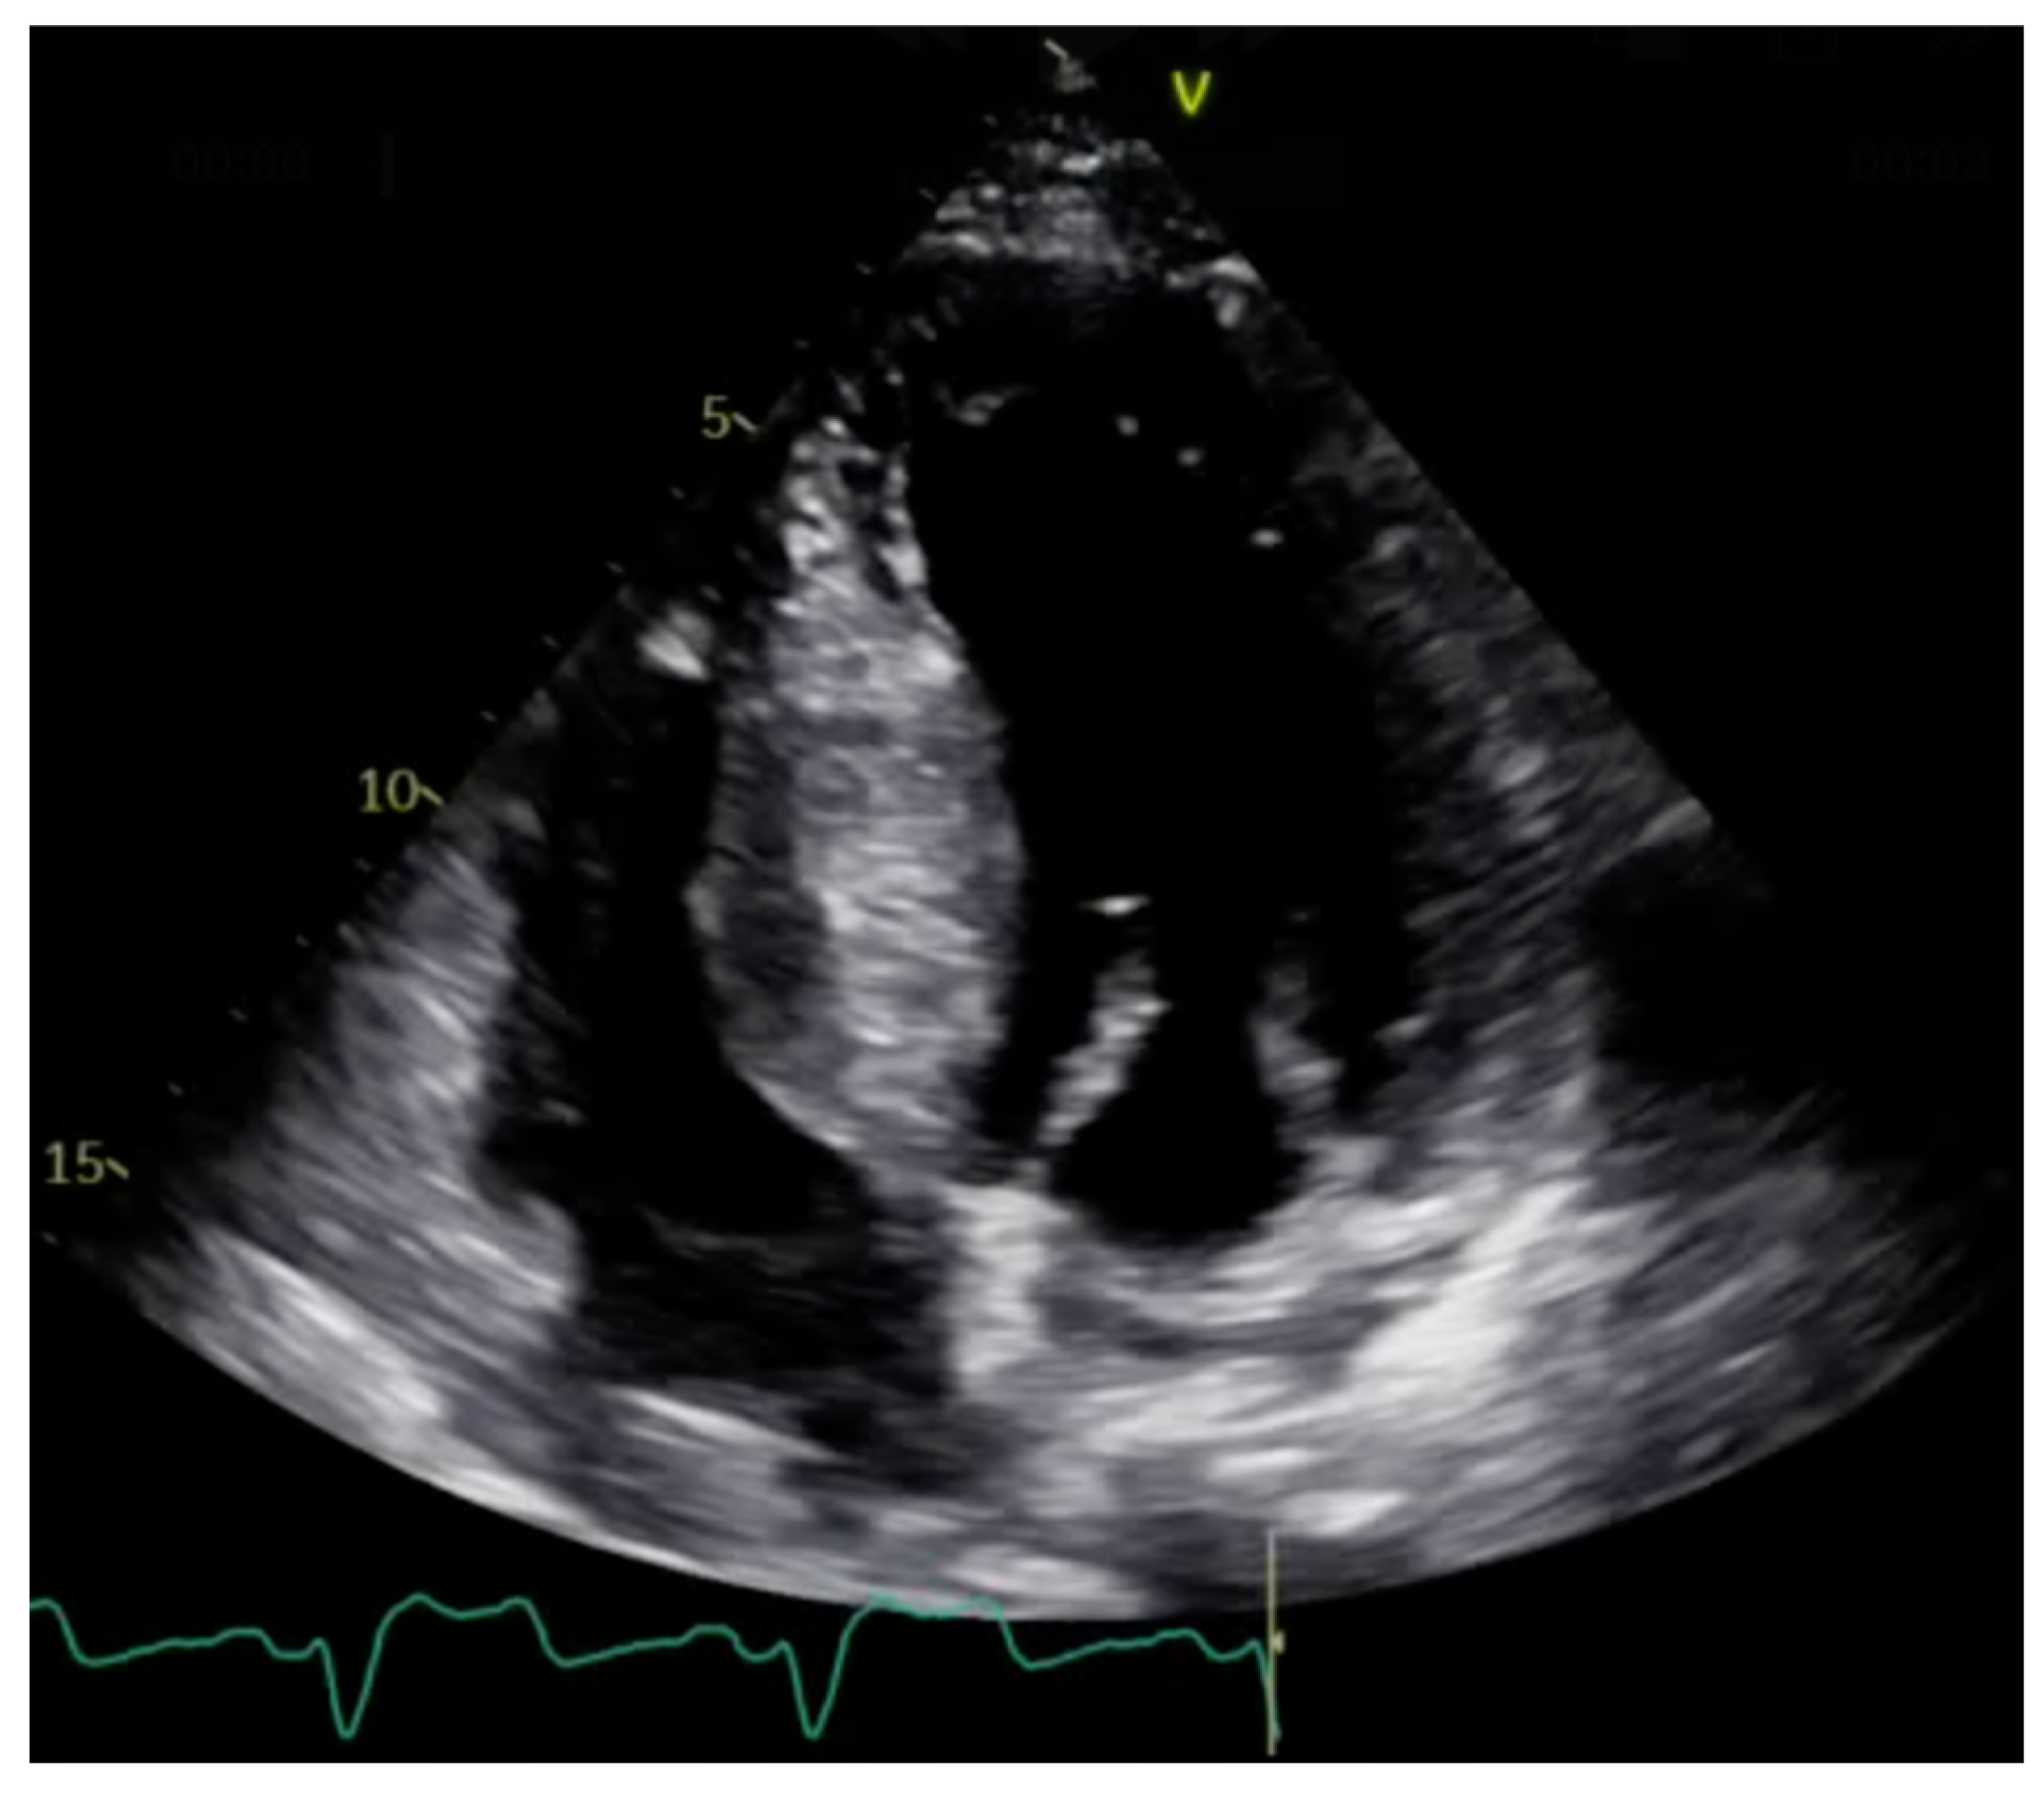

2.1. Echocardiography: The First Line of Diagnosis